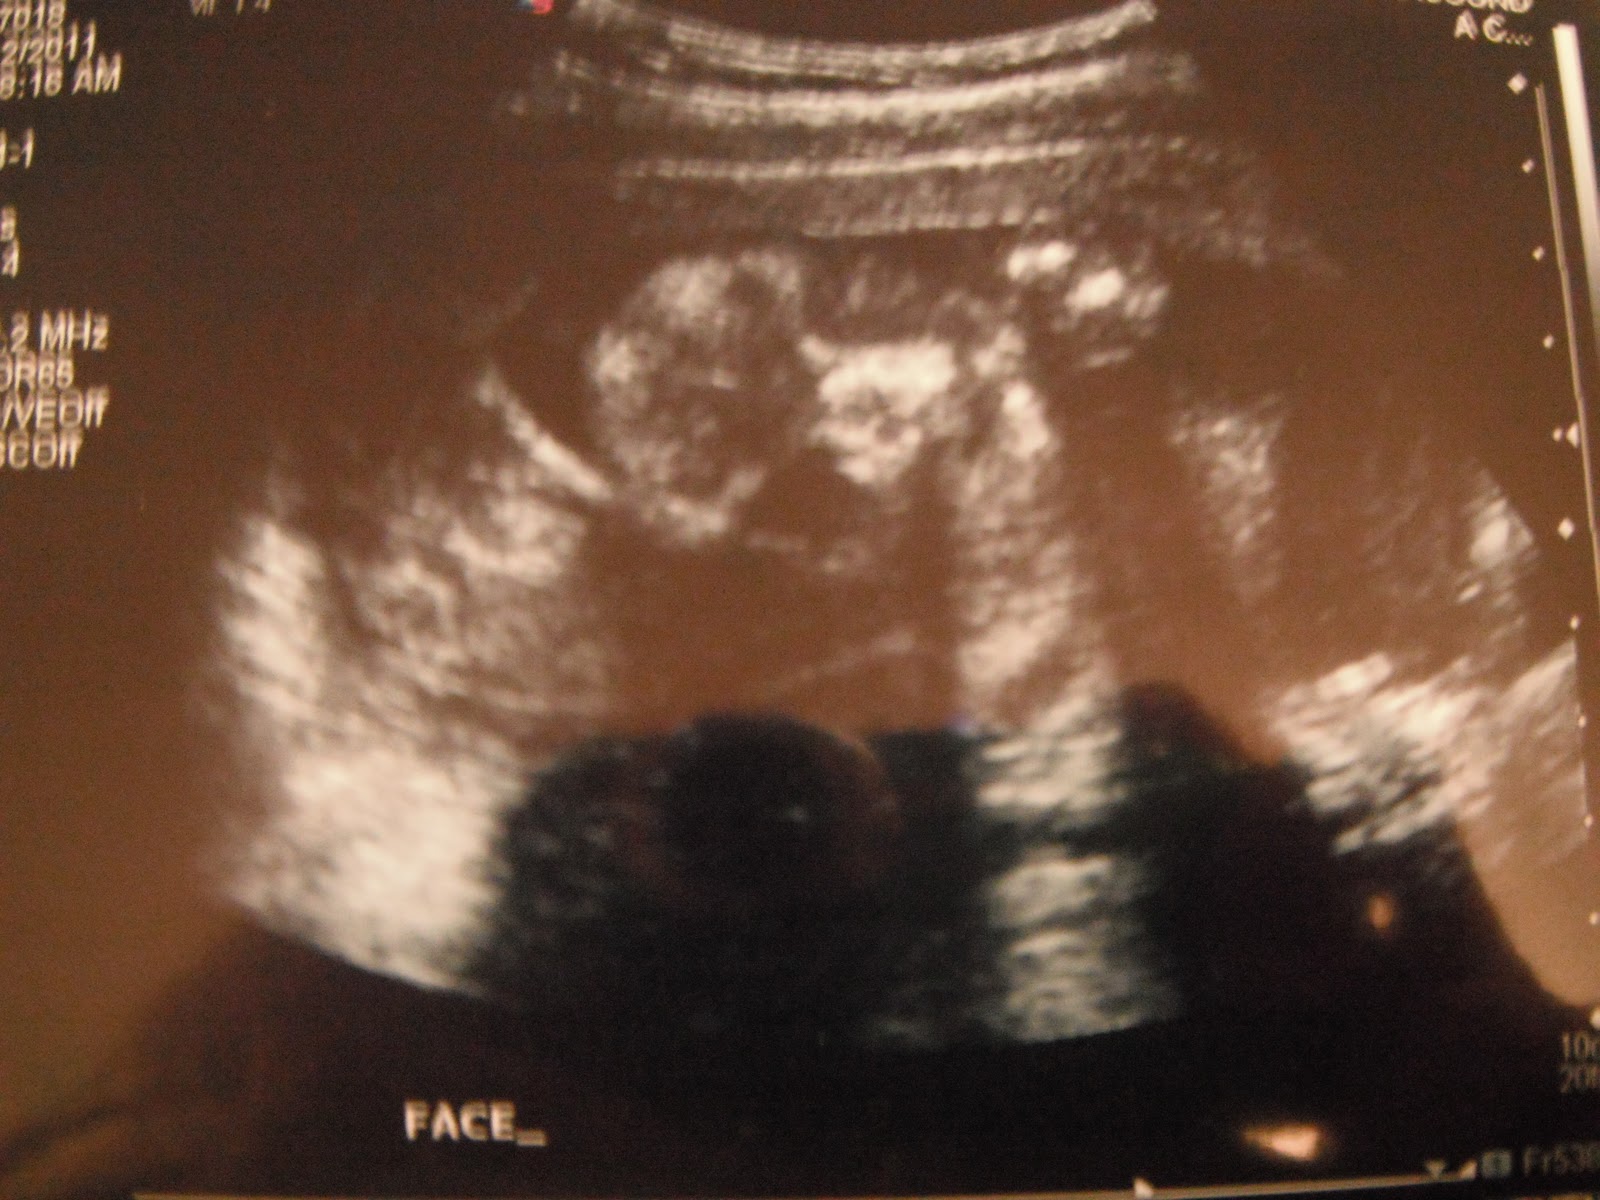

Face

Ian and I went in for our ultrasound at 19 weeks. We had our appointment at 8AM which meant I had to start drinking my 24oz of water way too early! ha ha. (I should have planned that one better) We were so excited and nervous for our ultrasound. When it came time to find out the gender our sonographer had to spend most of the appointment just getting him to move so that we could see what he was! I almost thought we were going to leave without knowing:( but luckily she didn't give up!